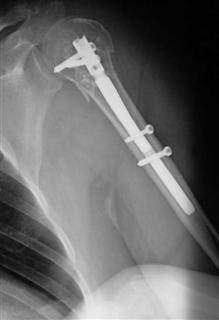

Оснащение Главного военного клинического госпиталя имени академика Н.Н. Бурденко позволяет диагностировать подобные травмы. а также, при использовании компьютерной томографии, осуществлять предоперационное планирование с предложением хирургических вмешательств различного объема и сложности. Наличие в госпитале трехмерной компьютерной томографии позволяет диагностировать скрытые переломы, избежать ошибок. Современные методы лечения, такие как, накостный остеосинтез пластинами, интрамедуллярный остеосинтез при внесуставных и внутрисуставных метаэпифизарных переломах плечевой кости позволяет осуществить раннюю активизацию пострадавшего и сократить сроки восстановительного периода. Выбор металлоконструкций позволяет обойтись без иммобилизации конечности и начать реабилитацию уже на следующий день после операции. Это особенно актуально для пациентов, ведущих активный образ жизни и пострадавших молодого возраста.